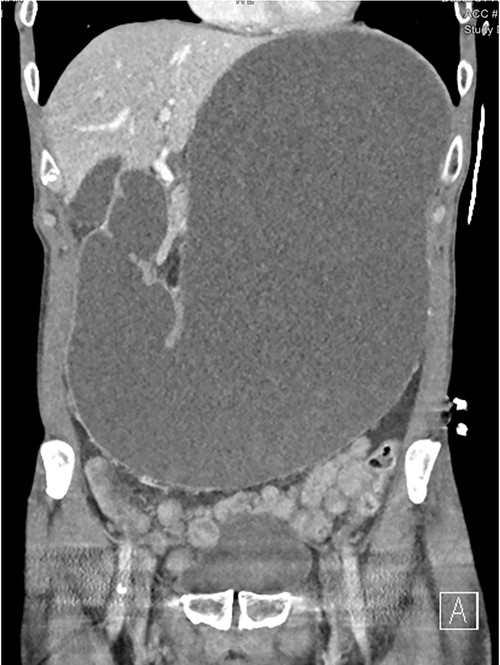

A 73-year-old male was transferred from a private hospital to the local public hospital 5 days post left total hip replacement with a 2-day history of nausea, bilious vomiting and colicky abdominal pain. His bowels had not opened since prior to the procedure. His background included previous right total hip replacement, benign prostate hyperplasia and depression. His medications included mirtazapine, tamsulosin, calcium carbonate and denosumab. He is a non-smoker and does not drink alcohol. On examination his observations were all within normal limits and he appeared to be very slim build. His height was 174 cm and he weighed 49 kg with a body mass index of 16.2. His abdomen was generally tender and distended, but not peritonitic. His blood results showed a serum potassium of 3.2 mmol/L, sodium 148 mmol/L, magnesium 0.94 mmol/L, albumin 34 g/L, creatinine 104 μmol/L, eGFR 61 ml/min (acute kidney injury), white cell count 7.7 × 109/L, haemoglobin 114 g/L. A computed tomography (CT) scan of his abdomen (Figs 1–3) showed a grossly distended stomach measuring 26.2 cm × 14.3 cm × 14.6 cm. It appeared fluid filled with moderate distension of the first and second part of the duodenum. The third part of the duodenum was partly fluid filled with an abrupt luminal collapse within the distal aspect where it passes between the superior mesenteric artery and aorta. The aorta mesenteric angle was reduced to ~23°. The remaining small bowel was decompressed with no free fluid or gas.

CT showing grossly distended stomach, first and second part of duodenum with sudden collapse and obstruction of duodenum (green arrow) at the superior mesenteric artery (blue arrow).

CT shows duodenum obstructed (orange arrow) between the aorta and superior mesenteric artery.